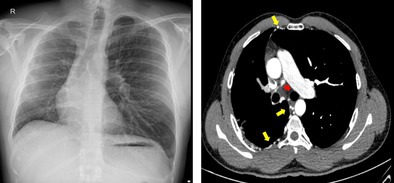

单侧肺动脉闭锁(UPAA)是一种罕见的先天性异常,其特征是缺少一条肺动脉。本文研究了三例UPAA,主要影响右侧,尽管有一例涉及左侧。常见的特征包括咯血,在两例患者中观察到,一例有慢性病史,需要栓塞,另一例是轻微的,最近发病。第三例是在术前评估时偶然发现的。所有病例均表现出不同程度的同侧肺体积缩小和相关间质改变或纤维化。UPAA可无症状或以咯血、反复感染或呼吸困难为表现。诊断依赖于计算机断层肺血管造影(CTPA)或磁共振血管造影(MR)。治疗方法从观察到栓塞或严重病例的全肺切除术。死亡率约为7%,肺动脉高压和出血是主要的预后因素。

Unilateral pulmonary artery atresia (UPAA) is a rare congenital anomaly marked by the absence of one of the pulmonary arteries. This article examines three instances of UPAA, predominantly affecting the right side, although one case involved the left side. Common characteristics included hemoptysis, observed in two patients-one with a chronic history necessitating embolization and another with a mild, recent onset. The third case was identified incidentally during a preoperative evaluation. All cases demonstrated varying degrees of ipsilateral lung volume reduction and associated interstitial changes or fibrosis. UPAA can be asymptomatic or present with hemoptysis, recurrent infections, or breathlessness. Diagnosis relies on computed tomography pulmonary angiography (CTPA) or magnetic resonance (MR) angiography. Management ranges from observation to embolization or pneumonectomy in severe cases. Mortality is around 7%, with pulmonary hypertension and haemorrhage being major prognostic factors.